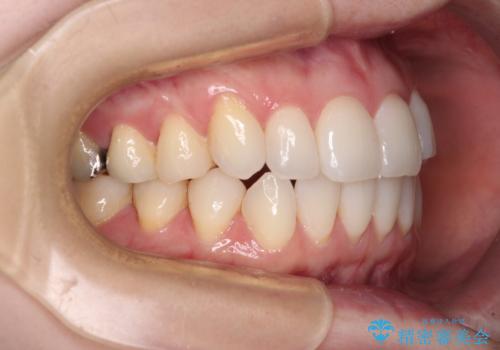

前歯のデコボコをインビザラインで改善

- 前歯のデコボコや八重歯の様になっていることを気にして来院された患者様です。

犬歯捻れて前方に飛び出しており、下顎前歯もそれに沿うようにデコボコとなっていました。

IPR(歯と歯の間を削る処置)によりスペースを獲得して上下顎前歯のデコボコを改善し、前歯が前方に突出しないように設定した上で、インビザラインにて矯正治療を行うこととしました。

途中体調を崩され、長い期間矯正治療を休むことになったため4年半ほどの治療期間がかかりました。